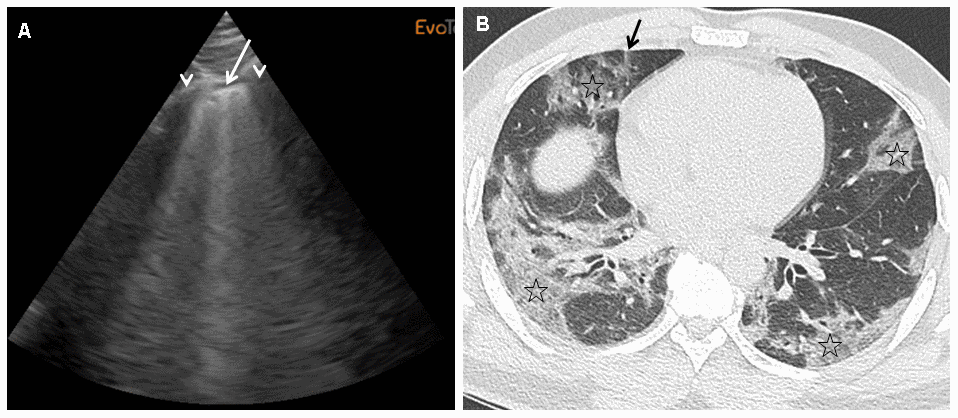

We performed daily bedside LUS evaluations using a portable device to evaluate COVID-19 pneumonia. LUS evaluations of lung damage were graded in the six categories described for ARDS, in a blinded manner for oxygen needs and CT scan grading, based on a twelve-point grading system (see Materiel and Methods section). We designed this severity index that is based on evaluations done with certainty to be able to take into account missing data and feasibility (see Material and Methods section for details). Table 2 reports the LUS scoring taking into account missing data, feasibility due to anatomical or posture problems, and oxygen requirements for the first 12 patients included. For the totality of the patients, the mean LUS severity score was 0.40 (ranging from 0.2 to 0.63). LUS exhibited 89% sensitivity and 100% specificity in predicting an abnormal CT scan with an AUC of 96% (95% CI) (Figure 1). When our LUS severity index was tested at different thresholds, we found that the value 0.32 was robust across sensitivity analyses, providing the optimal index to predict CT scan severity (Supplementary Table 1). Figure 2 illustrates the case of a 45-year-old man at 10 days from initial symptoms with severe pneumonia on CT scan. The LUS severity index was 0.58, with 10 locations scored from 1 to 4.

Figure 2. (A)This panel shows a grade 2 LUS image for a 45-year-old man at 10 days from initial symptoms, requiring oxygen (6 l/min), with a severity index of 0.58. On this sagittal ultrasound view encompassing a right anterior inter-rib space (arrows: rib shadows), one can see a typical lung rocket (arrow) as breath moving comet-tail artefact. (B) This panel shows an axial image of the corresponding CT scan performed at admission with typical COVID-19 interstitial pneumonia combining septal thickening (arrow) and peripheral ground glass opacities (stars).